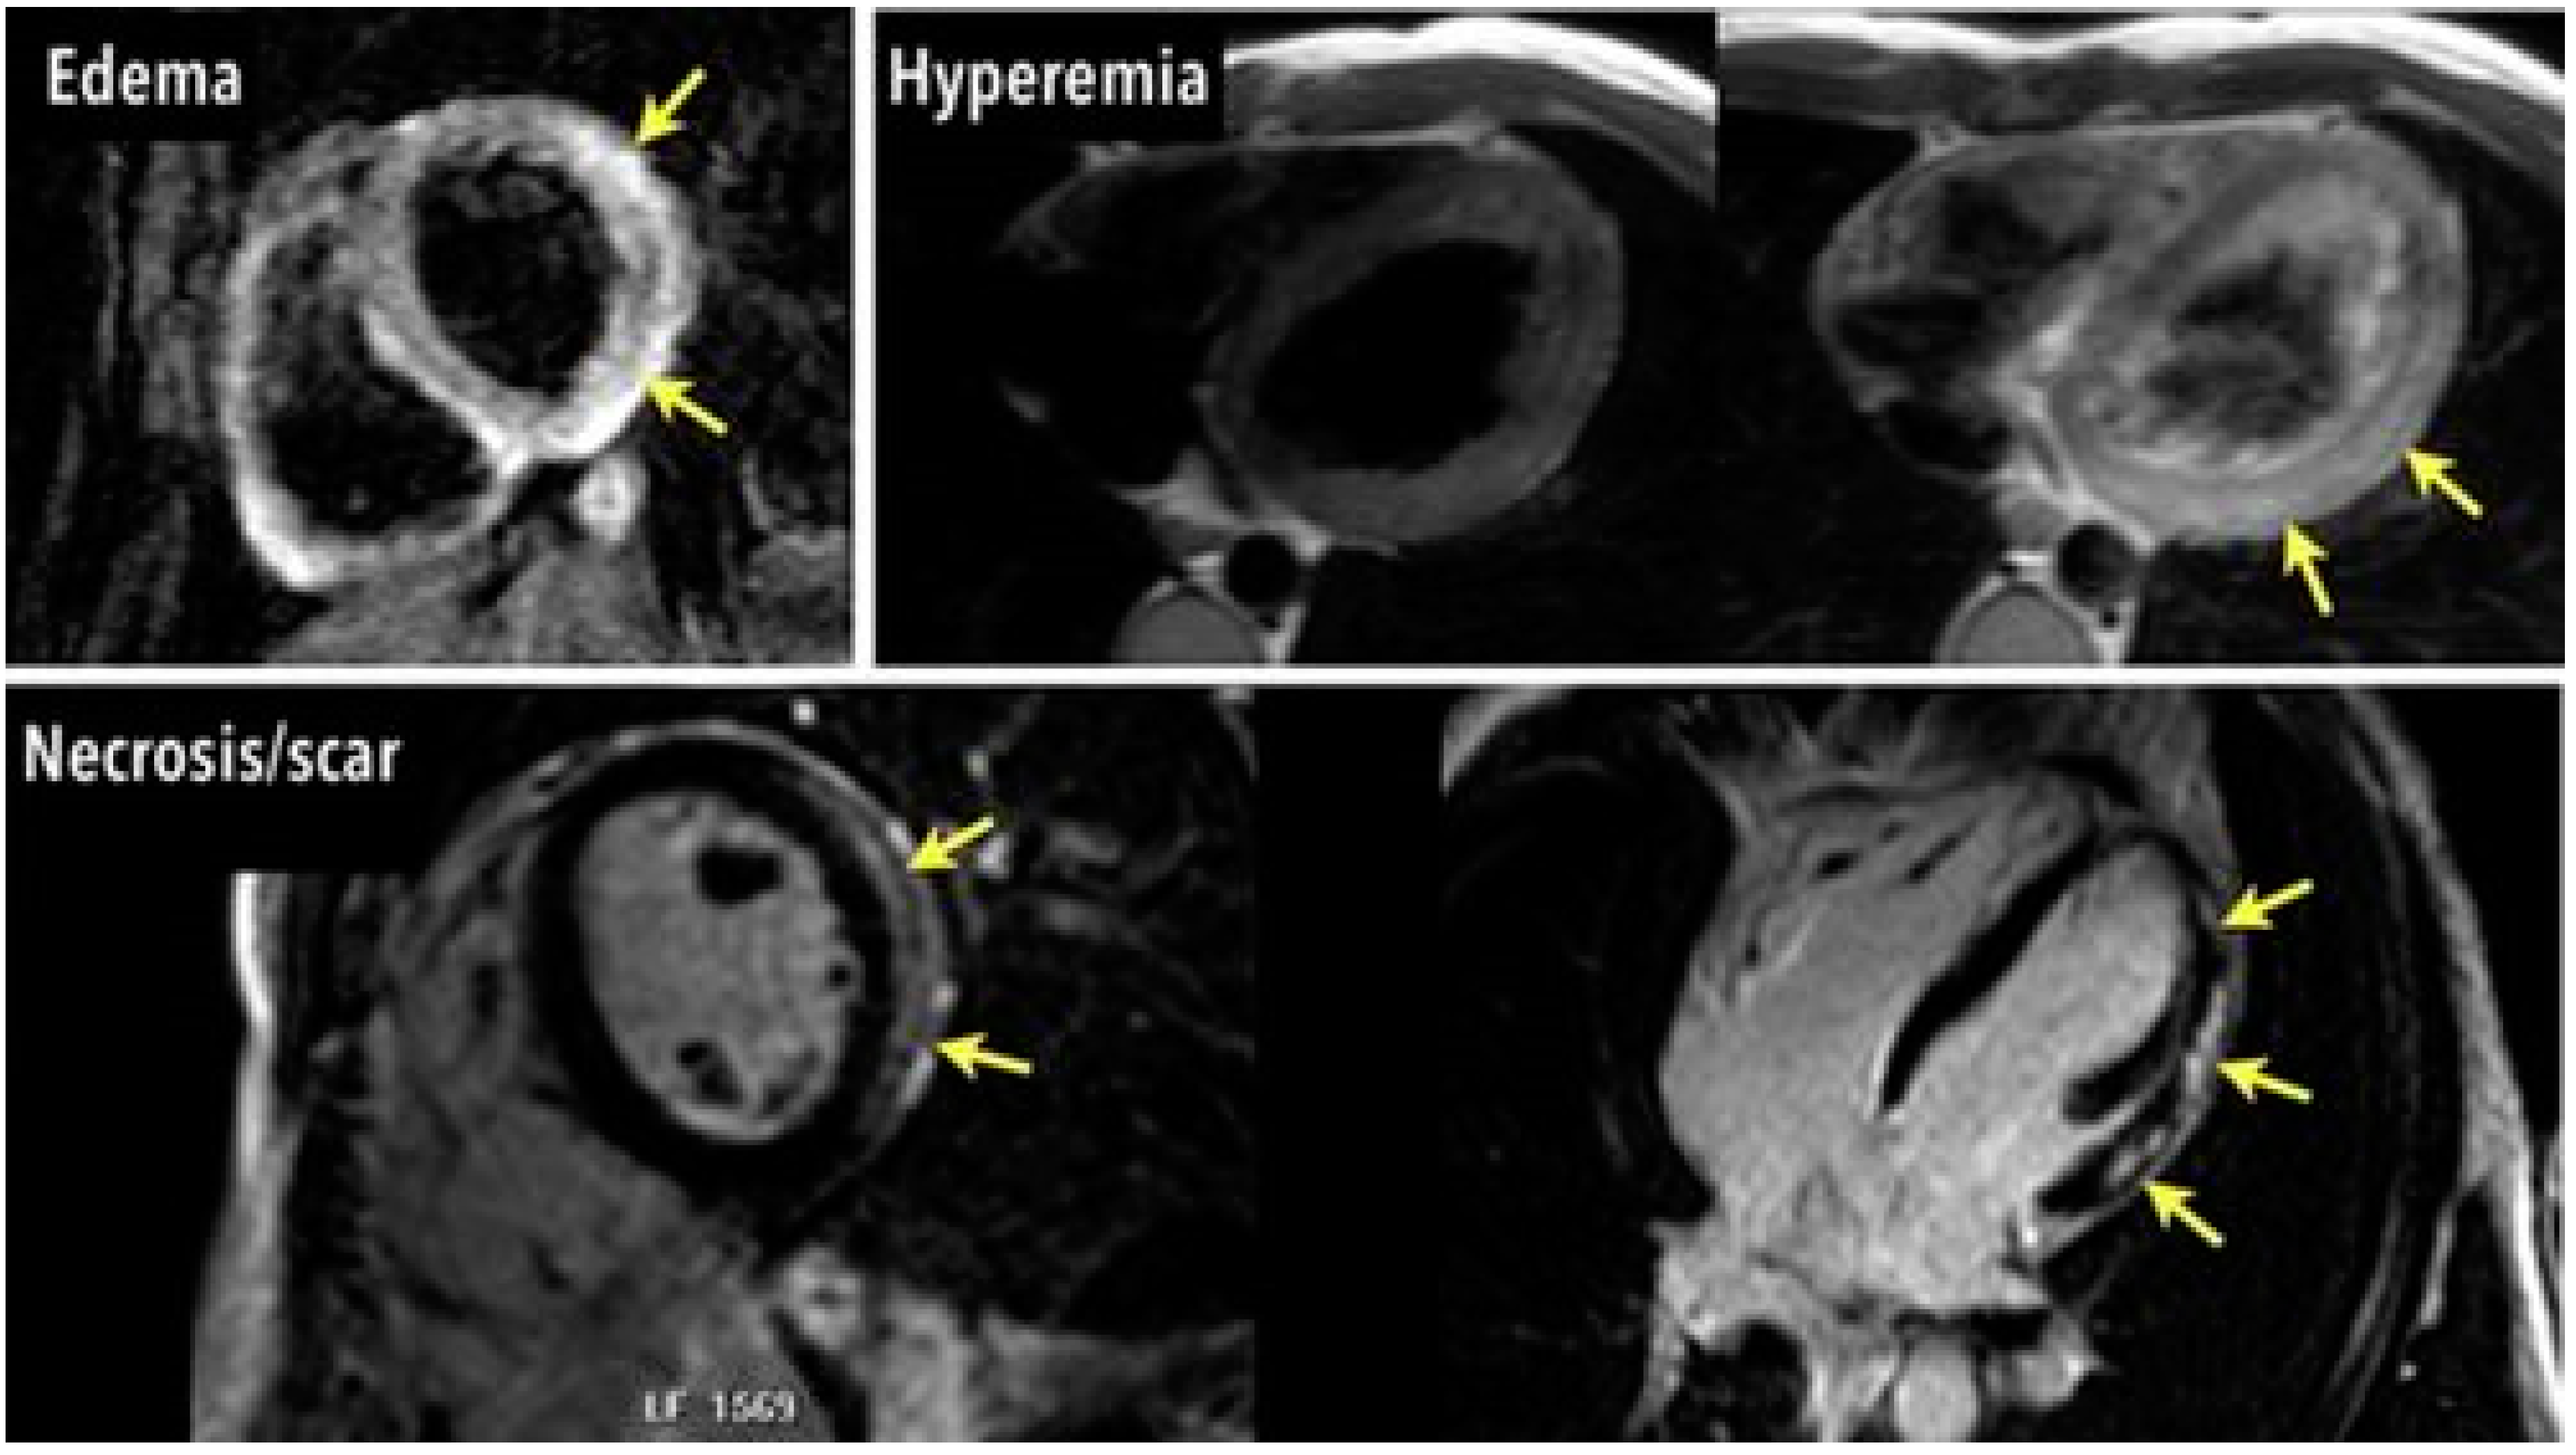

3.2.1. Myocardial Edema

3.2.2. Hyperemia and Extracellular Expansion

3.2.3. Fibrosis and Scar Formation